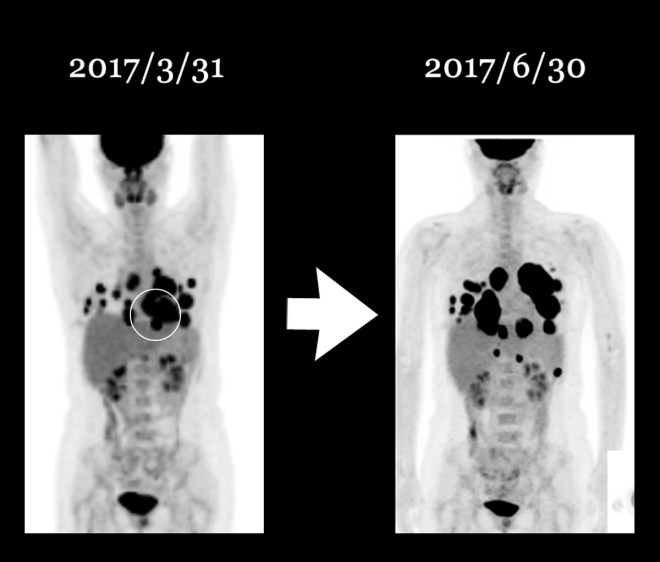

위에 보듯이 폐에 보이는 무수한 점들은 CT상에서는 더욱 선명하다. 다음에 PET에 나타나는 검은 점이나 CT상에서 동그란 솜 뭉쳐 놓은 것처럼 보이는 작은 원형의 점들이 모두 폐에 다발적으로 전이된 암을 표현한다.

1-10.jpg

서울대로 옮겨서 7 차 이후에 12 차까지 택솔을 시행하고 나서 종양이 매우 급속도로 폐에 전이가 되자 주치의는 약물을 바꾸어서 소음인 약물로만 구성된 gemcitabine하고 cisplatin을  2017년 3월부터 2017년 5월까지 시행하였다. 그리고 5월달 CT는 다소 종양의 감소를 보였다.

종양이 이같이 빠른 확산을 보이자 환자는 의사의 권유로 신약인 티센트릭을 사용하는 것에 동의 하였다. 티센트릭은 방광암 분야에서 현재 임상이 시도되고 있는 신약이다. 환자는 아래의 PET 사진에서 보듯이 일부는 3월에서 gemzar cisplatin이 4 차 시도되는 사이에 일부는 줄어들은 데도 있으나(원형 아래 부분) 결국은 나벨빈 사용 이후에 이같이 나빠지게 되었다.

1-14.jpg내가 여기서 나벨빈이 매우 강력한 태음인 약으로 소음인이 사용할 때 이렇게 나빠질 수 있다는 것은 모든 소음인에게 일어나지는 않지만 면역이 극도로 약화된 소음인들 경우에는 예외 없이 이같은 결과를 가져온다. 이는 서양의학이 항암제를 남용해서는 안 된다는 뜻이다.